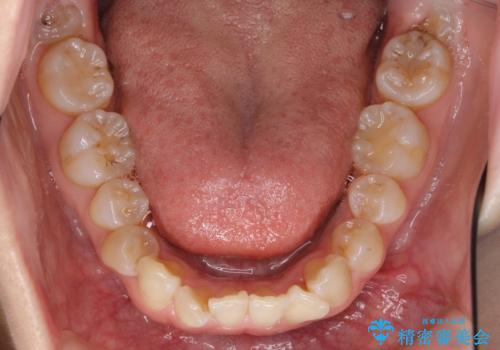

ハーフリンガル 犬歯のねじれ 歯根の外部吸収している歯を抜歯

- 前歯のねじれを主訴に来院。

レントゲンを撮影したところ、右下4は神経のない歯で、外部吸収といって、根がだんだん短くなり、やがて抜けてしまう症状になっていました。また、アンキローシスを起こしている可能性があるため、動かない可能性が高い状態でした。

矯正治療で右下を抜歯し、スペースを天然の歯でつめる矯正治療を行いました。